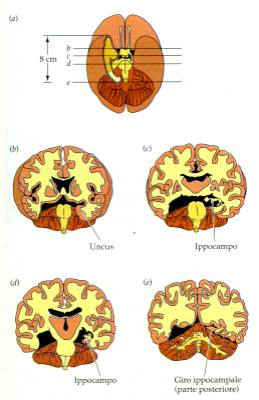

Ippocampo e corteccia

temporale

Un celebre caso clinico descritto da Milner e Scoville, il caso

del paziente HM ha chiarito come le lesioni dell'ippocampo e della

corteccia inferotemporale inducano gravi forme di amnesia.

Circuiti

dellippocampo

La stimolazione ripetuta di CA3

induce LTP in CA1

Ippocampo e memoria

umana.